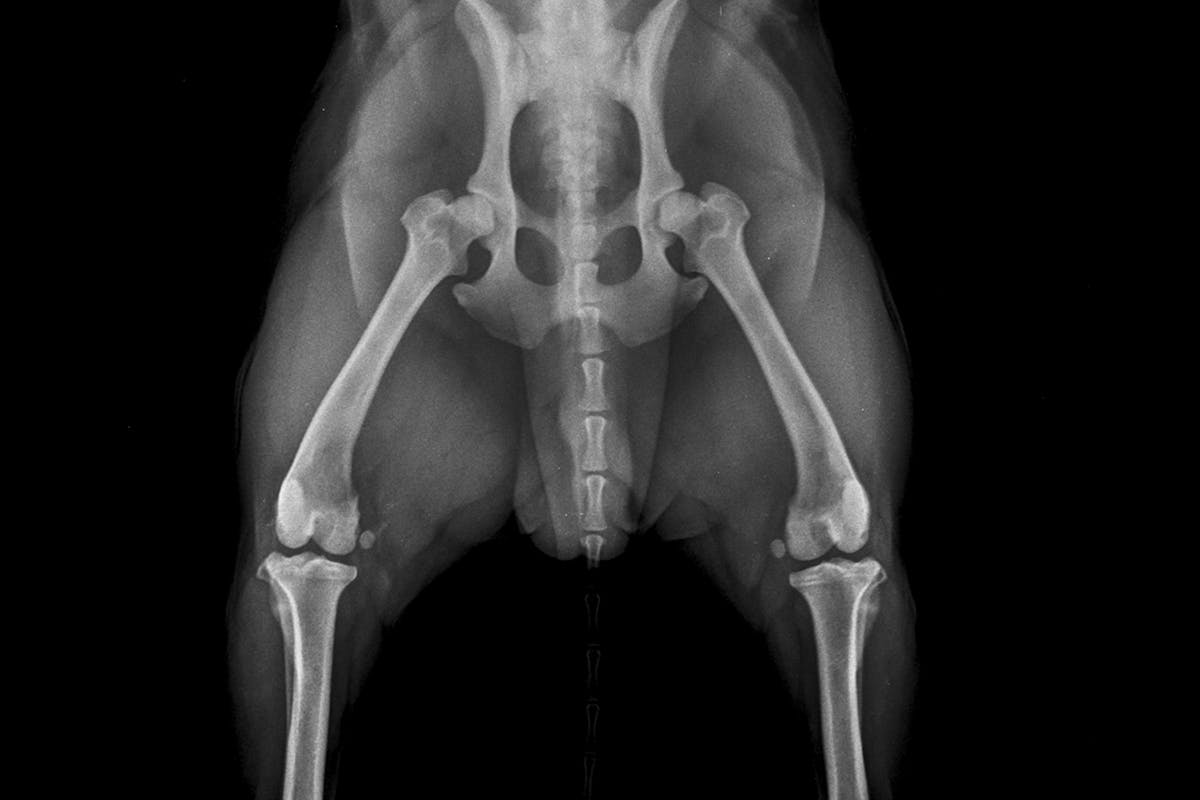

When the the ball and socket of a dog's hip joint do not fit together properly - problems can arise.

Hip dysplasia is when the hip joint becomes partially or completely dislocated- the ball and socket of the hip joint do not fit together properly. It is a complex condition involving both genetic and environmental factors that can cause varying degrees of pain and loss of function in the affected joint. The environment that a dog is raised in, as well as injuries, can play a significant role in the development of hip dysplasia. Diet and body condition of puppies will impact how the bones and joints develop; puppies who are not provided proper nutrition or who are overweight are at greater risk for orthopedic conditions.

Typically, when screening for hip dysplasia some form of chemical restraint, anesthesia or sedation is recommended for muscle relaxation allowing better positioning and a less fearful experience for the dog. Positioning of dogs to take radiographs does not result in or worsen hip dysplasia in any way- the procedure is a safe and effective way to screen dogs for the presence of the condition.

Submitted radiographs are independently reviewed by three randomly selected board-certified veterinary radiologists. Each radiologist assesses nine different anatomic areas of the joint for deviations consistent with hip dysplasia. Breed, age, and sex are also considered in the assessment. A grade is assigned based on the phenotype, or appearance, of the hip conformation:

Dogs must be at least 2 years of age to undergo the definitive screening as this has been determined to be the minimum age that the assessment is most reliable and predictive (Adams, 2000; Corley et al., 1997).